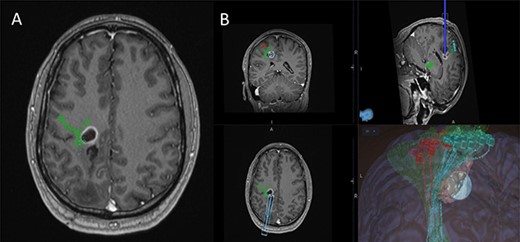

Intraoperative technical illustration: (A) transsulcal approach; (B) subdural strip of electrodes placed under preoperative nTMS and DTI guidance with stable responses at 7 mA; (C) docking of the BrainPath tubular retractor with positive responses of the anterior tibialis at 17 mA during the cannulation of the brain, insertion stopped at this point; (D) stimulation through the tube identified motor responses at 17 mA from lower limb muscles (tibialis anterior and abductor hallucis); (E) direct subcortical stimulation identified motor responses from upper and lower limb muscles at 7 mA; (F and G) Tumour subtotal resection stopped at 5 mA for the upper limb and 7 mA for the whole CST. The tumour demonstrated 5-ALA-induced fluorescence under the BLUE 400 filter; (H) activity from hand muscles at 5 mA threshold during removal of BrainPath tubular retractor before closure.

5-Aminolevulinic Acid (5-ALA) was given orally 2 h before the surgery. The least disruptive trajectory was selected taking into account the previous biopsy and the preoperative mapping information (Fig. 3). Under Stealth guidance, a skin incision was made overlying the planned craniotomy site. After the craniotomy, the dura was opened and a subdural strip of electrodes was placed over the primary motor cortex. Replicable motor responses from the hand muscles were obtained at 7 mA current intensity (Fig. 4). Motor evoked potentials (MEPs) were obtained continuously throughout the procedure. A transsulcal parafascicular approach was used. The sulcus was opened sharply under the microscope. At the depth of the sulcus, a preselected tubular retractor (NICO BrainPath 75 mm × 13 mm) was passed to the superficial surface of the lesion. While performing brain cannulation to the lesion, a monopolar probe (INOMED©) navigated with SureTrack (MEDTRONIC©) was used to perform continuous subcortical stimulation, train-of-five technique using high-frequency stimulation.

Once the superficial aspect of the lesion was reached, positive stimulation of the lower limb was identified at 17 mA (Fig. 4). The tubular retractor was fixed with a Leyla retractor system and held manually to prevent displacement. Multiple tissue samples were obtained from 5-ALA-induced fluorescent tissue. Intraoperative smear was consistent with high-grade lesion. After the biopsy was performed the tubular retractor was slowly removed. Using a monopolar probe for subcortical stimulation directly through the surgical site, we were able to confirm the proximity to the CST at 5 mA to the lower limb motor fibres. Cortical MEPs were stable during the whole procedure.